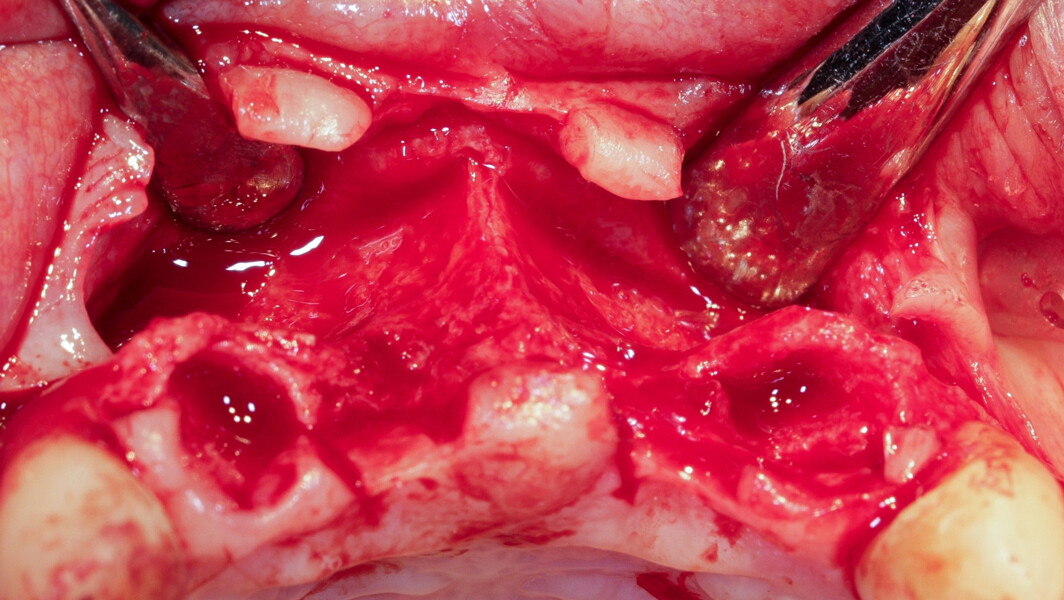

Pour se faire il a été décidé d’exploiter les racines extraites (11 et 21) pour reconstruire la paroi vestibulaire des alvéoles. Nous réalisons un lambeau avec une incision sulculaire de 13 à 23, en prenant soin de préserver les papilles interdentaires, ainsi que deux décharges verticales en distal des canines. Nous réalisons un décollement de pleine épaisseur (Fig. 11). Les dents sont facilement extraites et les alvéoles curetées avec soins. Deux implants (4*10) sont positionnés dans la paroi palatine des alvéoles, il subsiste une déhiscence vestibulaire (Fig. 12). La racine de 11 est séparée dans le sens de la longueur en deux fragments. Les racines préparées comme indiqué ci-dessus, sont vissées en vestibulaire de la crête au moyen de deux vis d’ostéosynthèse (diamètre 0,9 mm) afin de reconstruire la paroi vestibulaire (Figs. 13 et 14). L’espace entre l’implant et le greffon est comblé avec un matériau synthétique (Collapat II, SYMATESE). Le lambeau est tracté, suturé coronairement avec un fil tressé synthétique 5.0 (Fig. 15). Une empreinte est prise à la fin de l’intervention, le provisoire, préparé dans la journée par notre laboratoire de prothèse est vissé le soir même (Fig. 16). L’implant 21 ayant un couple de serrage insuffisant pour être mis en fonction, il s’agit d’un provisoire cantilever, direct implant, vissé sur l’implant 11 (Fig. 17).

À l’examen la patiente présente en vestibulaire, au niveau de 11 et 21, des pertes de substances importantes (osseuses et gingivales), particulièrement en 21 avec la destruction de l’intégralité de la paroi vestibulaire de la crète, et une perte totale d’ancrage de la racine, ainsi qu’un frein labial inséré haut sur la crête. On conserve néanmoins l’architecture des tissus mous avec la présence de papilles interdentaires et un volume osseux apical suffisant pour permettre l’ancrage des implants (Figs. 8–10). L’enjeux du traitement est de réaliser les extractions, de poser les implants, de reconstruire la crête osseuse, et de mettre en place des provisoires fixes sur les implants, en conservant l’architecture des tissus mous.